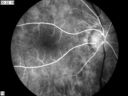

CRAO352 viewsCRAO in OD Late Phase of FA

CRAO386 viewsCRAO in OD Tranisit Phase of FA

CRAO340 viewsCRAO in OD Tranisit Phase of FA

CRAO415 viewsCRAO Color Montage